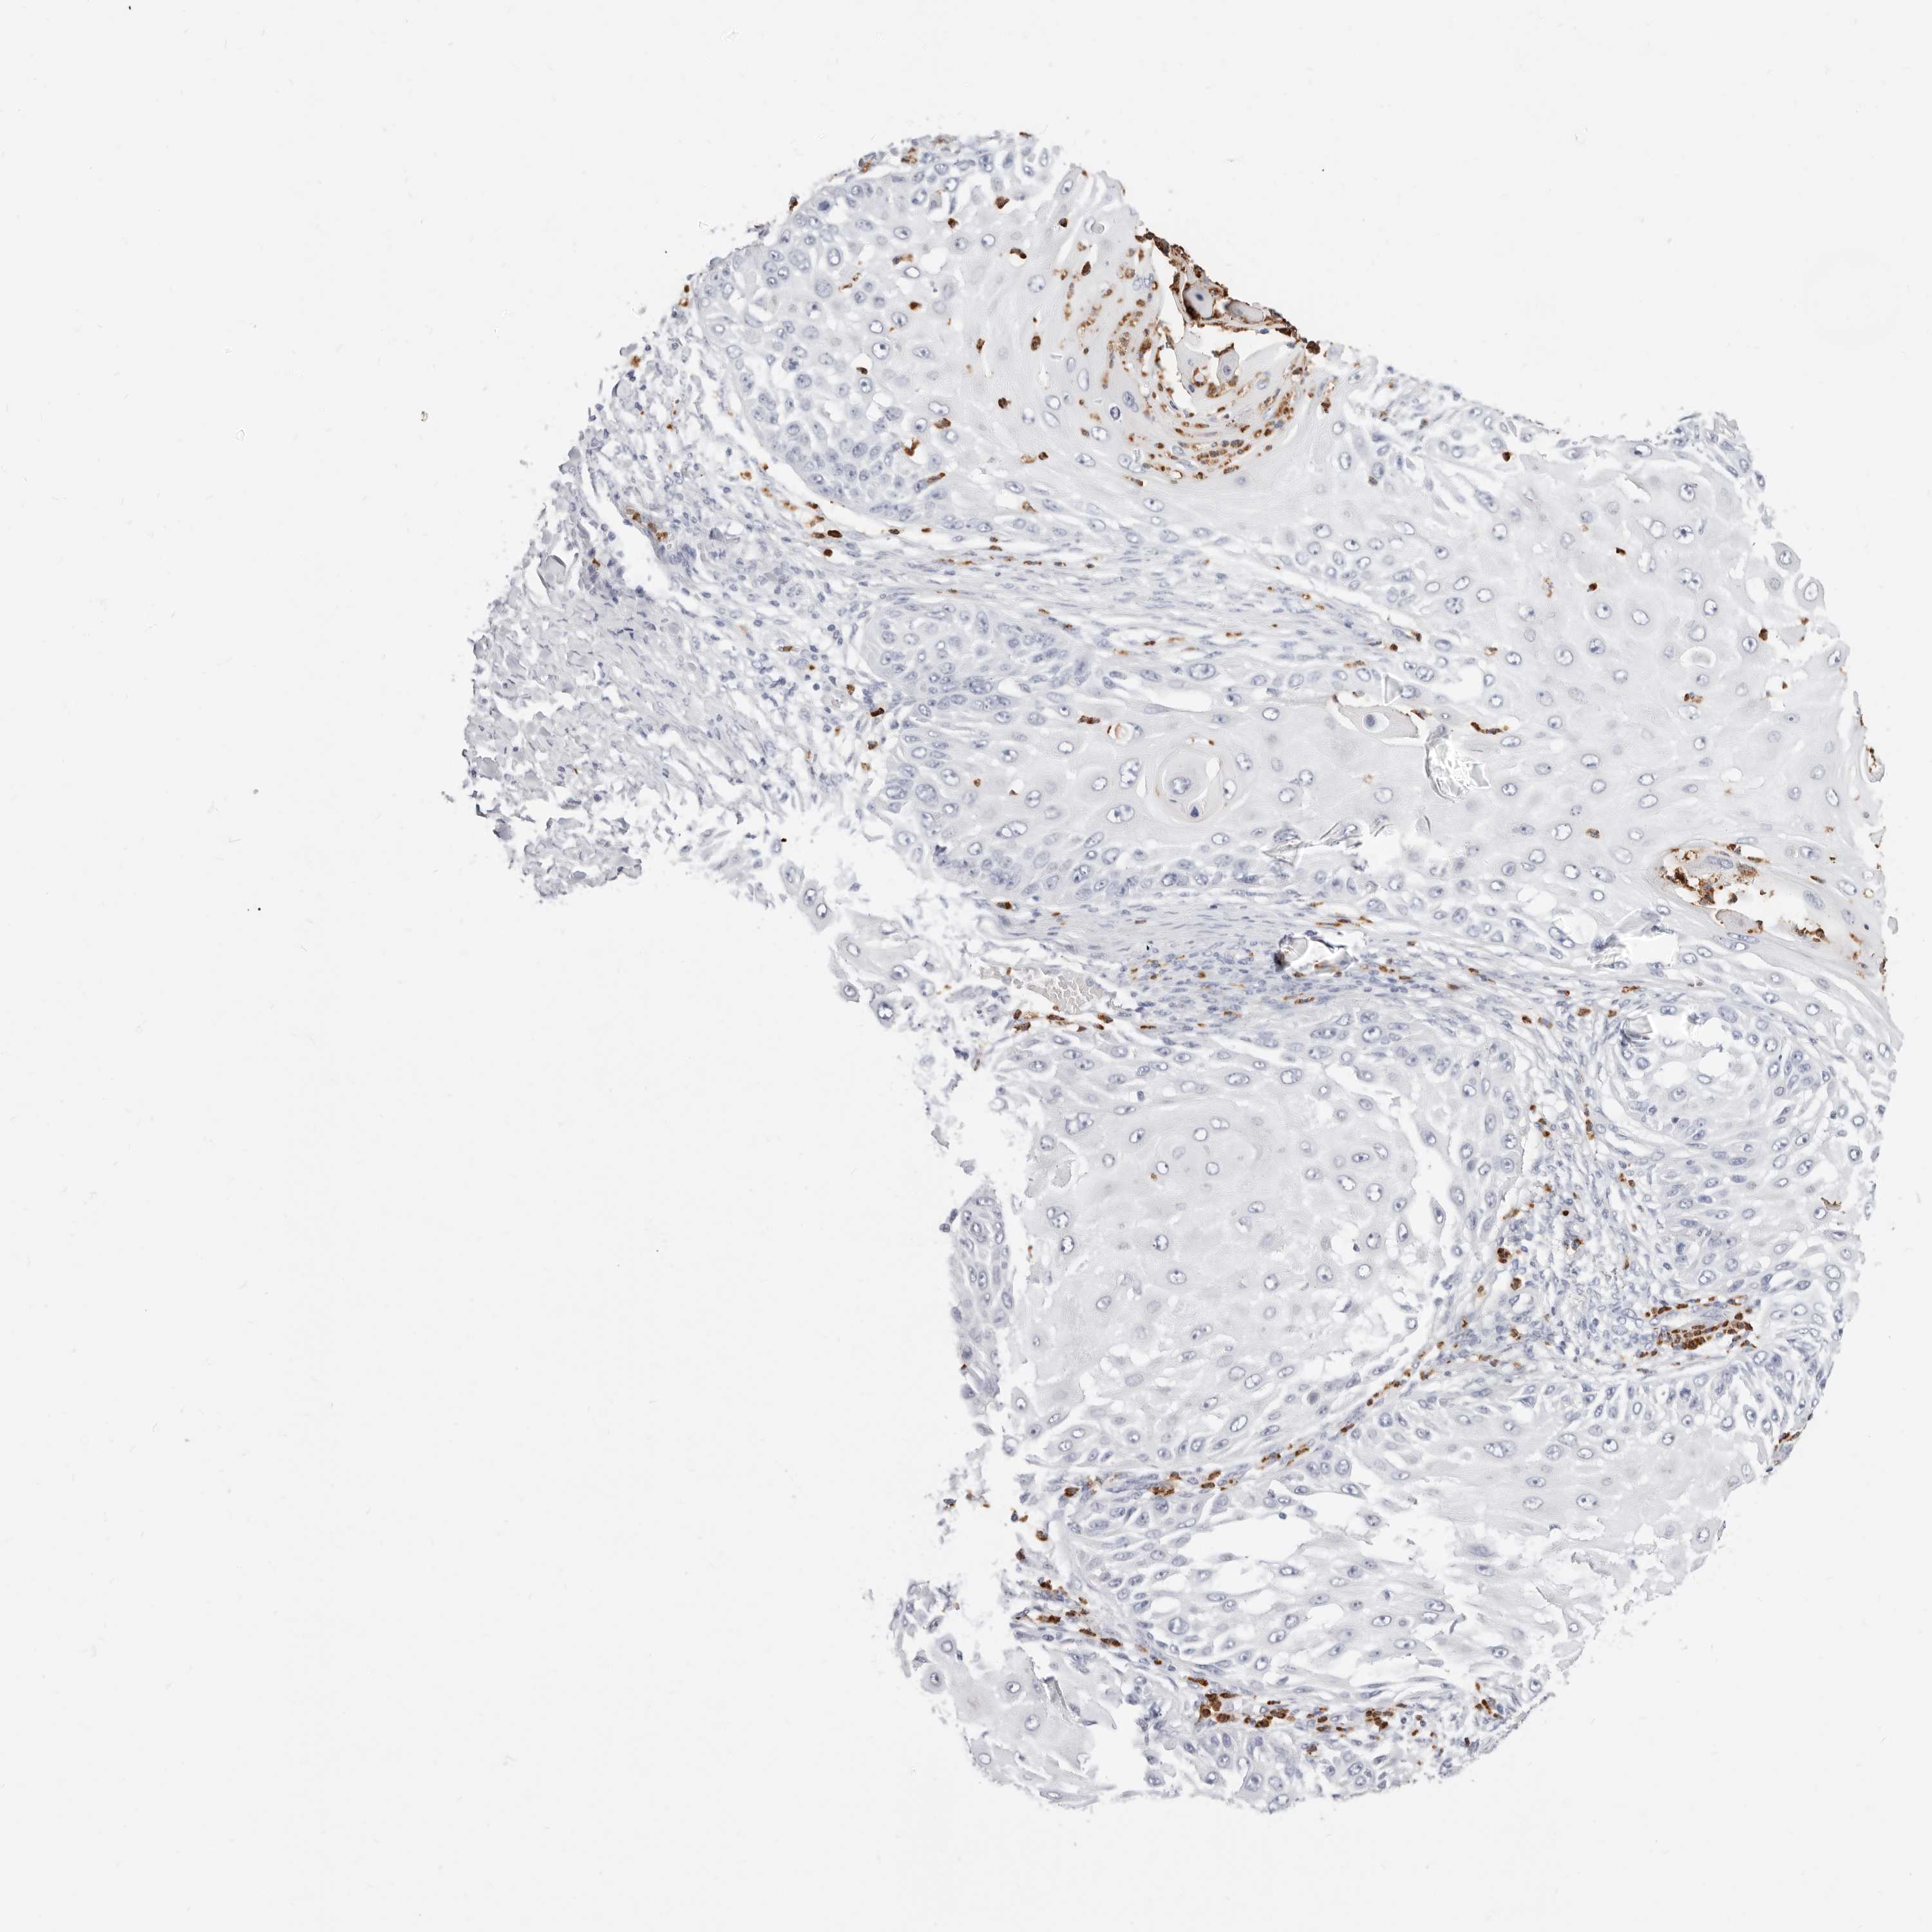

SKIN CANCER - Protein expressioni

A mouse-over function shows sample information and annotation data. Click on an image to view it in a full screen mode. Samples can be filtered based on level of antibody staining by selecting one or several of the following categories: high, medium, low and not detected. The assay and annotation is described here.

Antibody stainingi

Antibody staining in the annotated cell types in the current human tissue is reported as not detected, low, medium, or high, based on conventional immunohistochemistry profiling in selected tissues. This score is based on the combination of the staining intensity and fraction of stained cells.

Each image is clickable and will lead to virtual microscopy that enables deeper exploration of all samples and also displays staining intensity scores, fraction scores and subcellular localization as well as patient and tissue information for each sample.

Antibody CAB015949

Squamous cell carcinoma, NOS